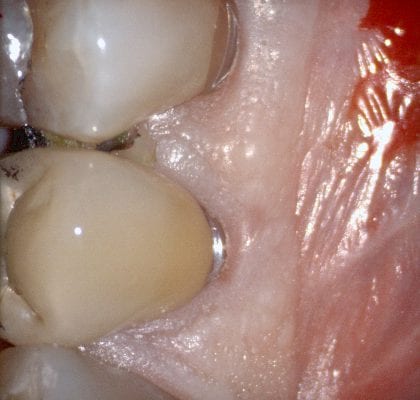

In this case presentation, we utilize the medit i500 to image the pre-existing crown and to fabricate a restoration that is a replica of the pre-existing condition. The patient was advised that the recurrent decay was in close proximity to the canal space and that endodontic treatment may be a possibility. The CBCT showed no evidence of any peri-apical radiolucency and the premolar tested vital prior to treatment

Case set up involved imaging the pre-existing condition in the pre-op catalog box. Excess information was cropped to reduce file size. The data was then copied to the maxillary arch catalog box and the area to prepared was edited out in preparation for final optical impressions.